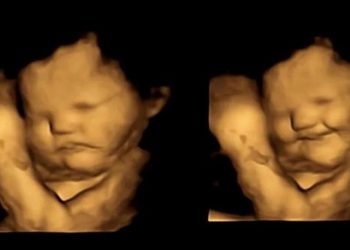

Araştırma: Anne karnındaki bebekler anneleri havuç yiyince gülümsedi

Yeni bir araştırma, bebeklerin daha anne karnındayken farklı tatlara tepki vermeye başladığını gösterdi. Durham Üniversitesi’nden araştırmacılar, 100 hamile kadın üzerinde ...